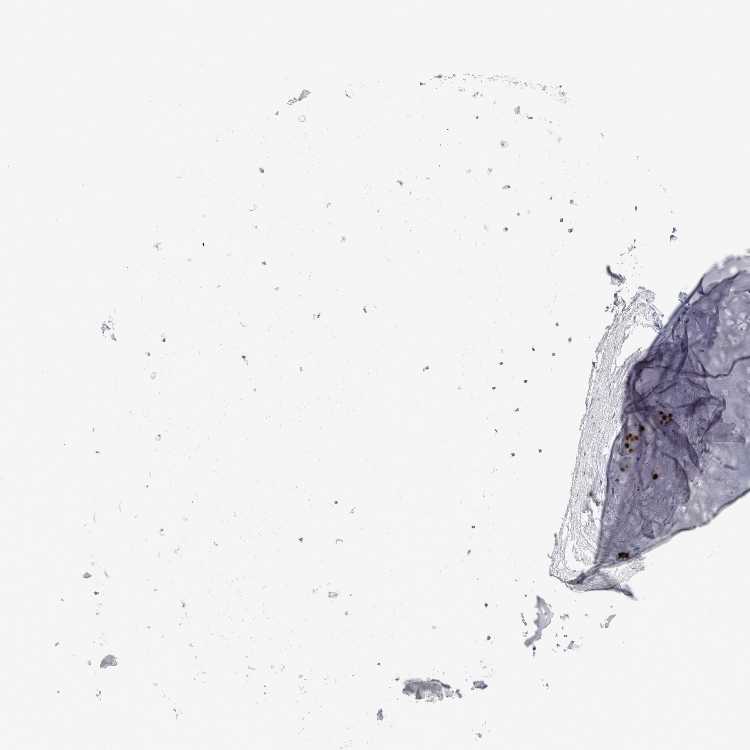

SOFT TISSUE 1 - Antibody stainingi

Antibody staining in the annotated cell types in the current human tissue is reported as not detected, low, medium, or high, based on conventional immunohistochemistry profiling in selected tissues. This score is based on the combination of the staining intensity and fraction of stained cells.

Each image is clickable and will lead to virtual microscopy that enables deeper exploration of all samples and also displays staining intensity scores, fraction scores and subcellular localization as well as patient and tissue information for each sample.

Antibody HPA024372Antibody CAB002791

Chondrocytes Not detected-

Fibroblasts Not detectedNot detected